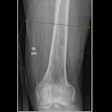

| Above, Dr. Arthur Newberg reads an exam at the Polyclinic. |

Then, as if on cue, sports medicine specialist Dr. Mark Lento arrived to consult with Newberg on an MRI of a fractured wrist. Lento called the images "beautiful," and Newberg credited the Polyclinic MR technologists for producing such high-quality work.